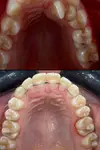

Crooked Teeth